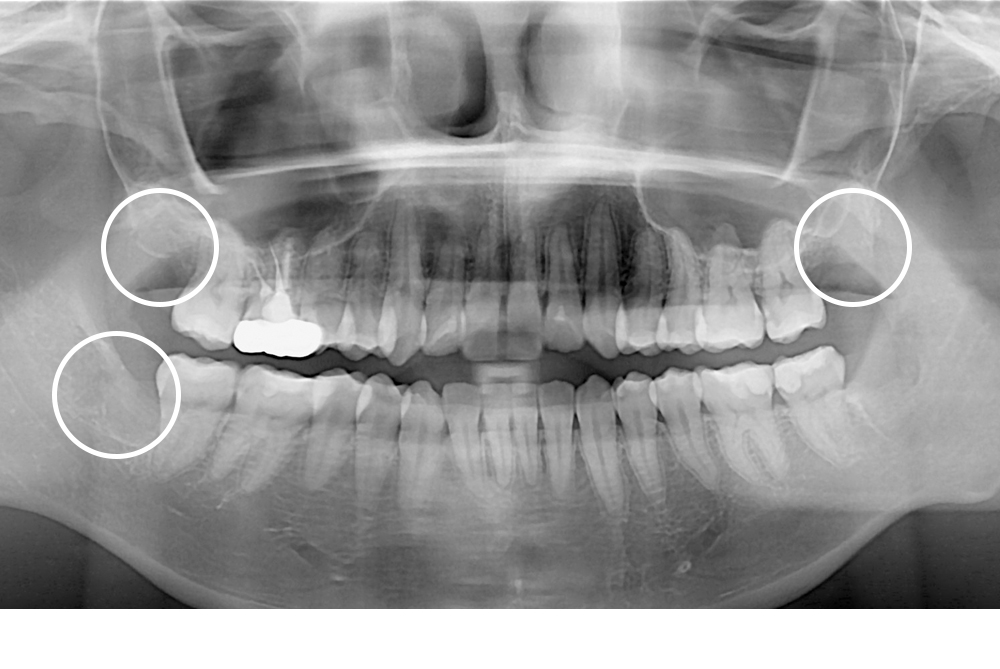

[사랑니] 매복 사랑니 발치

치료전 : 2019-02-14

세종치과는 구강악안면외과학 박사이신 원장님이 발치하는 치과입니다.